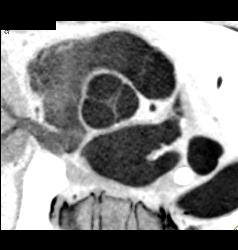

Diagnosis

Normal Aortic Valve